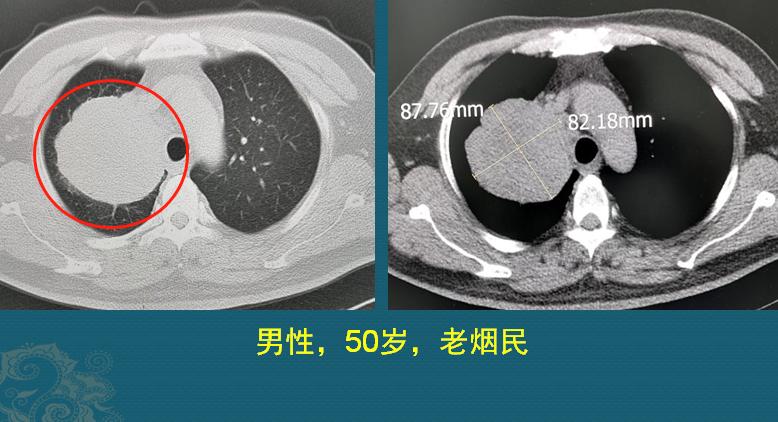

这是一位50岁男病人,有吸烟史35年,因为咳嗽、咳痰20天,自服止咳药和抗生素无效,呼吸科医生建议他做了胸部CT,发现8.7cm的大肿瘤:

应该说,癌症病人的运气很重要,运气有时跟癌细胞的病理类型有关,他这个肿瘤尽管超过了8cm,并没有发生远处转移,在胸外科顺利切除。手术后病理分型为中分化肺鳞癌,癌细胞侵犯脏层胸膜,并且在切下来的15枚淋巴结中,有2枚发现癌细胞转移,分期属于T3N1M0。